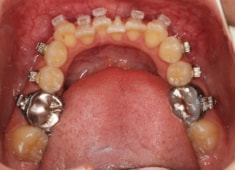

治療開始時

治療中